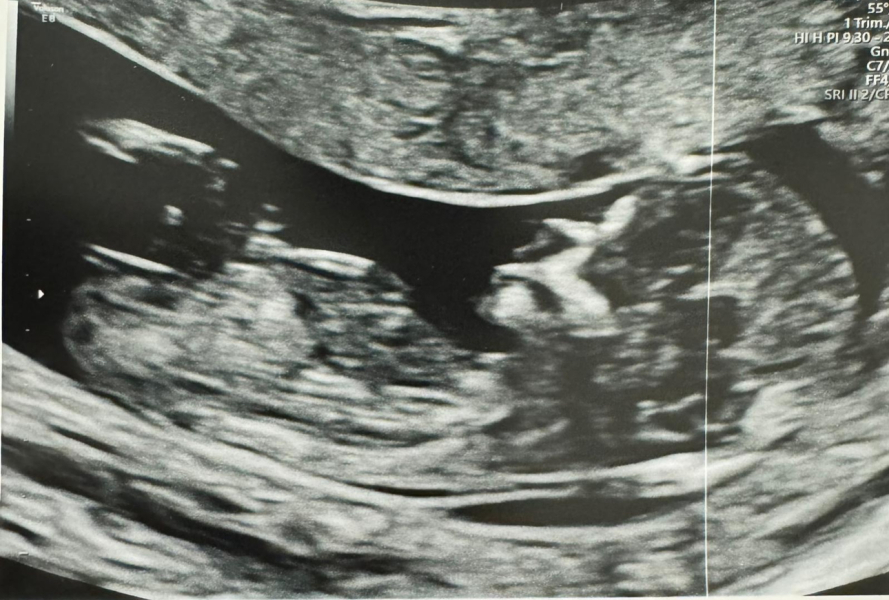

peardeer · 19/04/2024 19:20

Thank you for asking 🌈 It went perfectly 🥹🤍 I can't believe it. This is officially the furthest we have ever got. Feeling so emotional and so grateful x

And a very clear nub! Are you finding out?

@AppleTree16 I would love to know! A few people have said clear nub but I have no clue! What do you think it is? X

@peardeer I think it's a girl!

@CluelessInLondon someone else has said this! I would love either but my husband would love a girl 🌈🤍

@peardeer looks very girly to me! How many weeks are you? If you’re 12ish weeks it could still change and move up though. (I only found out this fact a few weeks ago!)

@Bee49 I'm 13+3, I still can't work out where the numb is 😂

@peardeer I’m definitely voting girl! Very inexperience but think it’s here? (Just waiting for someone to tell me I’m all wrong 😂)